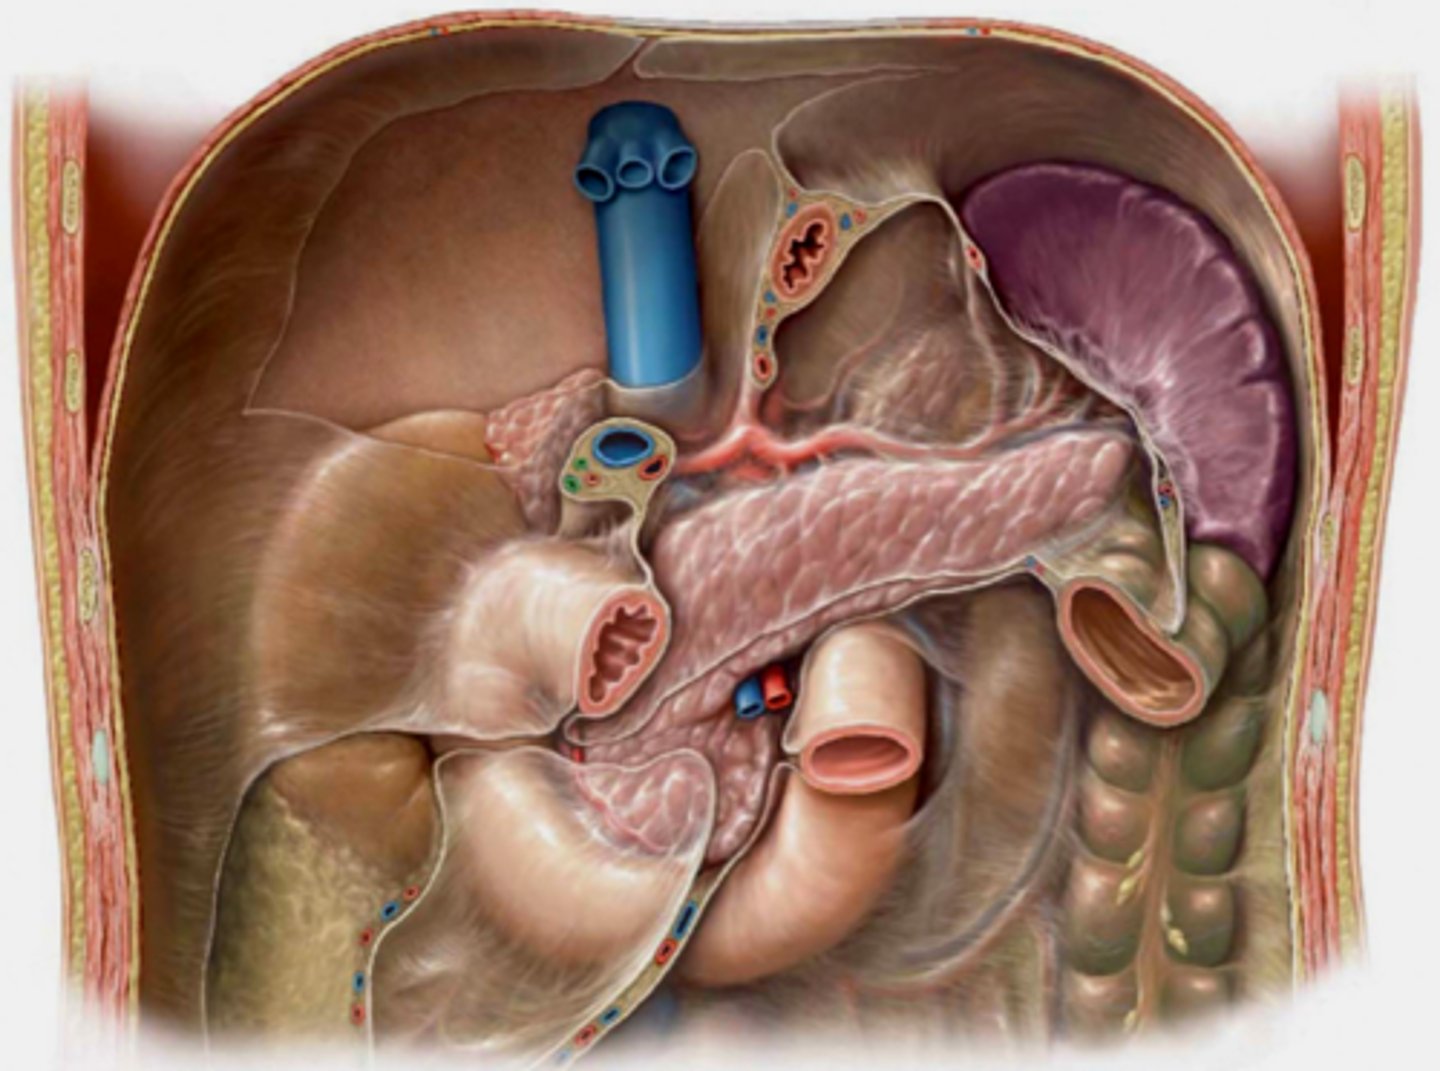

Identify pertinent anatomy in the following radiograph

knowt flashcard image

SMA

<p>SMA</p>

Identify pertinent anatomy of the following radiograph

1. Celiac Trunk 2. Splenic artery 3. Spleen 4. Left Gastric 5. Common Hepatic 6. Proper Hepatic 7. Gastroduodenal 8. Pancreaticoduodenal (don't have to be able to identify for test!) 9. Right gastroepiploic 10. Left gastroepiploic

<p>1. Celiac Trunk 2. Splenic artery 3. Spleen 4. Left Gastric 5. Common Hepatic 6. Proper Hepatic 7. Gastroduodenal8. Pancreaticoduodenal (don't have to be able to identify for test!) 9. Right gastroepiploic 10. Left gastroepiploic</p>